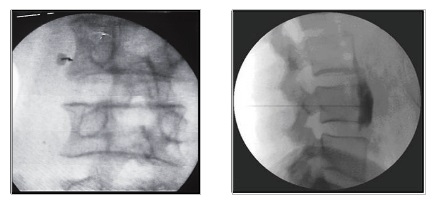

Τα οσφυϊκά συμπαθητικά γάγγλια εδράζονται στο προσθιοπλάγιο τριτημόριο του δεύτερου, τρίτου και τέταρτου οσφυϊκού σπονδύλου. Με τον ασθενή σε πρηνή θέση και με τοπική αναισθησία, εισάγονται κάτω από ακτινοσκοπικό έλεγχο διαδοχικά 3 βελόνες, οι οποίες προωθούνται στα πλάγια τον σπονδυλικών σωμάτων με το άκρο τους να φθάνει στο πρόσθιο 1/3 των σπονδυλικών σωμάτων. Χορηγείται σκιαγραφική ουσία και επί ικανοποιητικής απεικόνισης, χορηγείται το διάλυμα τοπικού αναισθητικού και στεροειδούς. Για μακρά θεραπευτική δράση, απαιτούνται διαδοχικές συνεδρίες φαρμακευτικού αποκλεισμού ή νευρόλυση με χρήση ραδιοσυχνοτήτων.